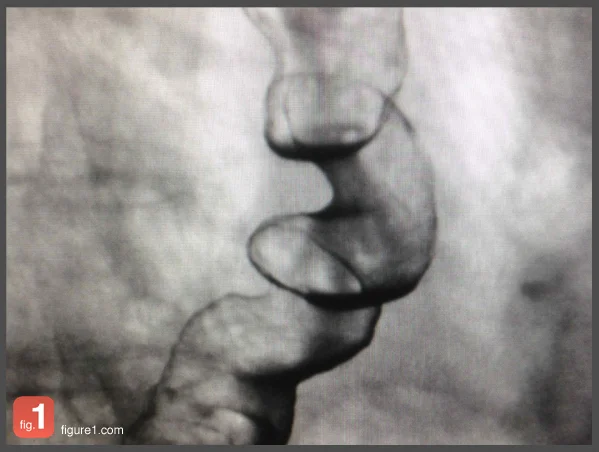

Not all chest pain is cardiac. The patient above had been experiencing intermittent substernal chest pain with radiation to the back for the past year associated with eating too quickly. They also endorsed a history of heartburn and dysphagia. Scroll down to reveal the diagnosis.

Diffuse Esophageal Spasm

Corkscrew esophagus, or diffuse esophageal spasm, is a relatively rare esophageal motility disorder. Due to minimal available information on the pathogenesis of this occurrence, it is unclear whether this abnormality represents a distinct disorder. The trademark of this form of dysmotility is the presence of excess simultaneous contractions in the distal esophagus, although a number of other motility patterns may be observed. As pictured here, barium radiographic images include severe non-peristaltic contractions which produce abnormalities in the barium column.